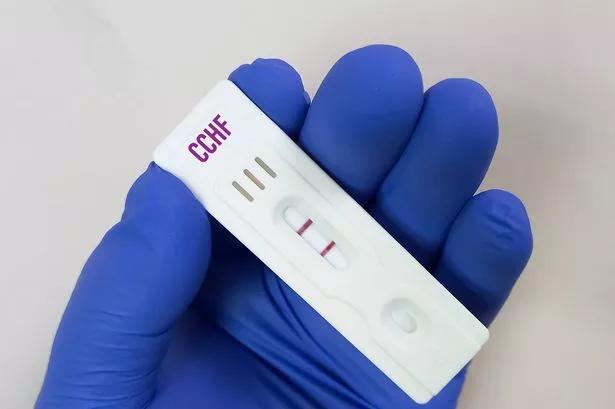

The Nimbus Variant: A Menacing Recap Read more

Health officials have issued a warning about a fast-spreading new strain of Covid-19, which comes with unusual symptoms. Read more

Unveiling the Range of Symptoms Linked to Newly Discovered Covid Strain in Northern Ireland

The full list of symptoms caused by a new variant ofcoronavirusthat's now been detected in Northern Ireland has been announced. Read more